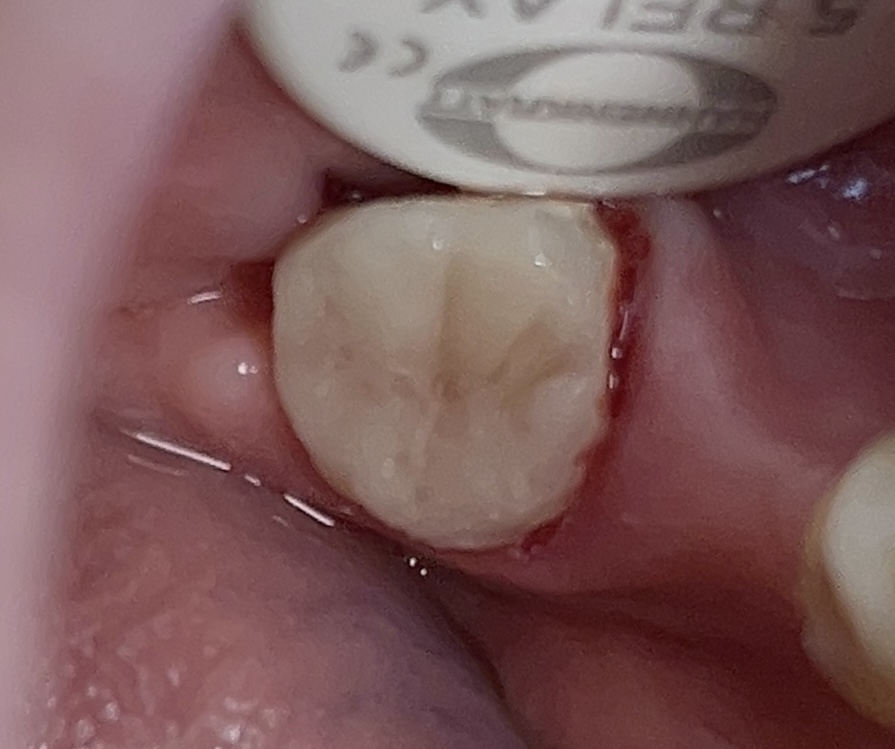

Clinically:

Chronic irritation of the pulp resulted in a polyp over each canal orifice.